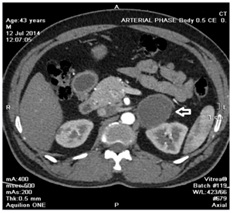

On clinical examination, pulse rate was 88/min, regular and blood pressure was 150/90mm Hg. Electrocardiogram showed sinus rhythm with heart rate of 80/min. His blood counts, liver function tests and renal function tests were within normal range. Transthoracic echocardiogram showed mild left ventricular hypertrophy with Left Ventricular Ejection Fraction (LVEF) of 69%. Serum amylase and lipase were within normal range. HbA1C was 6.5%. TSH was 9.4mIU/L, 24 hrs urine metanephrine and normetanephrine were significantly elevated [Table/Fig-1]. The 320 slice CT of abdomen showed 5cm x 4.3cm x 4.3cm cyst in the left adrenal gland with fine septations inside and cholelithiasis [Table/Fig-2]. In view of possibility of pheochromocytoma, MIBG scan was done, which showed faint MIBG concentration in the left adrenal cyst. MRI of abdomen showed left adrenal mass (4.3cm x 4.4cm x 4.8cm), acute calculous cholecystitis and probable early pancreatitis.

CT scan image showing adrenal cyst.